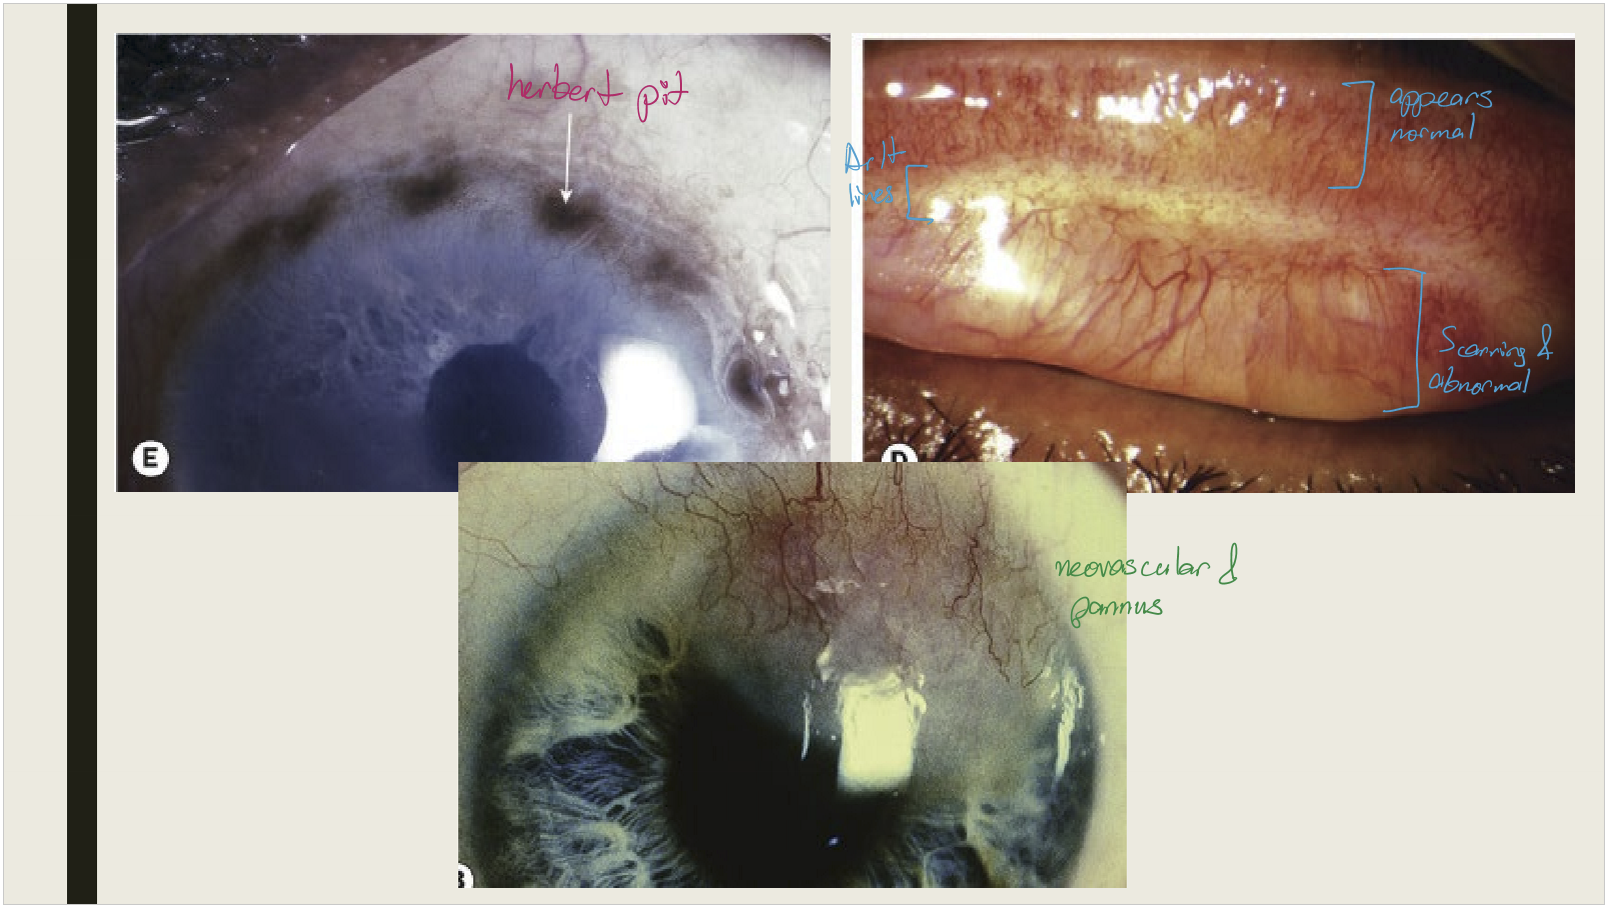

What happens to superior limbal follicles after they resolve in cicatricial trachoma?

They leave shallow pits (Herbert pits)

<p>They leave shallow pits (Herbert pits)</p>

Mixed papillary + follicular reaction, mucopurulent discharge, superior epithelial keratitis, pannus formation

<p>Mixed papillary + follicular reaction, mucopurulent discharge, superior epithelial keratitis, pannus formation</p>

Conjunctival scarring

• Mild infection: linear or stellate scarring

• Severe infection: broad confluent scared (Arlt lines)

• Superior tarsal effected more then other areas of conjunctiva

<p>Conjunctival scarring </p><ul><li><p>Mild infection: linear or stellate scarring</p></li><li><p>Severe infection: broad confluent scared (Arlt lines)&nbsp;</p></li><li><p>Superior tarsal effected more then other areas of conjunctiva&nbsp;</p></li></ul><p></p>

What are the corneal and eyelash changes seen in cicatricial trachoma?

Corneal opacification with vascularization; trichiasis and distichiasis

<p>Corneal opacification with vascularization; trichiasis and distichiasis</p>